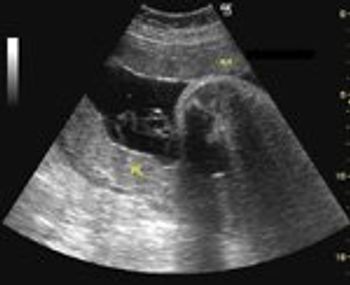

This is an ultrasound scan of the placenta.

In this protocol, Dr. Hankins reviews the pathophysiology, diagnosis, and management of external cephalic version. Included are step-by-step guidelines for performing the procedure with illustrations of the maneuvers required for successful cephalic version with 2 operators or 1. As the author notes, careful assessment of fetal presentation in the third trimester is important. Otherwise, patients may be deprived of the option of external cephalic version to decrease the risk of cesarean delivery. Before the procedure, fetal well-being and the presence of any contraindications should be ascertained. Informed consent and counseling with regard to the likelihood of success of the procedure should be performed. Post-version assessment for fetal presentation on subsequent encounters is vital in these patients.